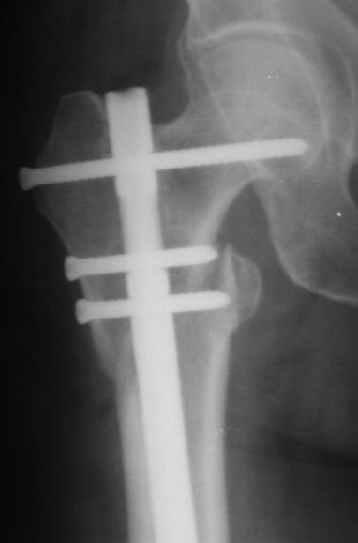

Могу скромно напомнить о существовании стержня нашей модификации.

В частности, на проксимальном конце сделано еще одно дополнительное статическое отверстие. Можно ввести в проксимальном отделе 4 винта, из них 3 статические (2 в круглые отверстия и 1 по нижнему краю овального). Картинки в приложении. На дистальном конце стержня тоже кое-что улучшено. Спрашивайте в аптеках, как говорится. Выпускается предприятием "ЦИТО" (Москва), то есть это малобюджетное решение.